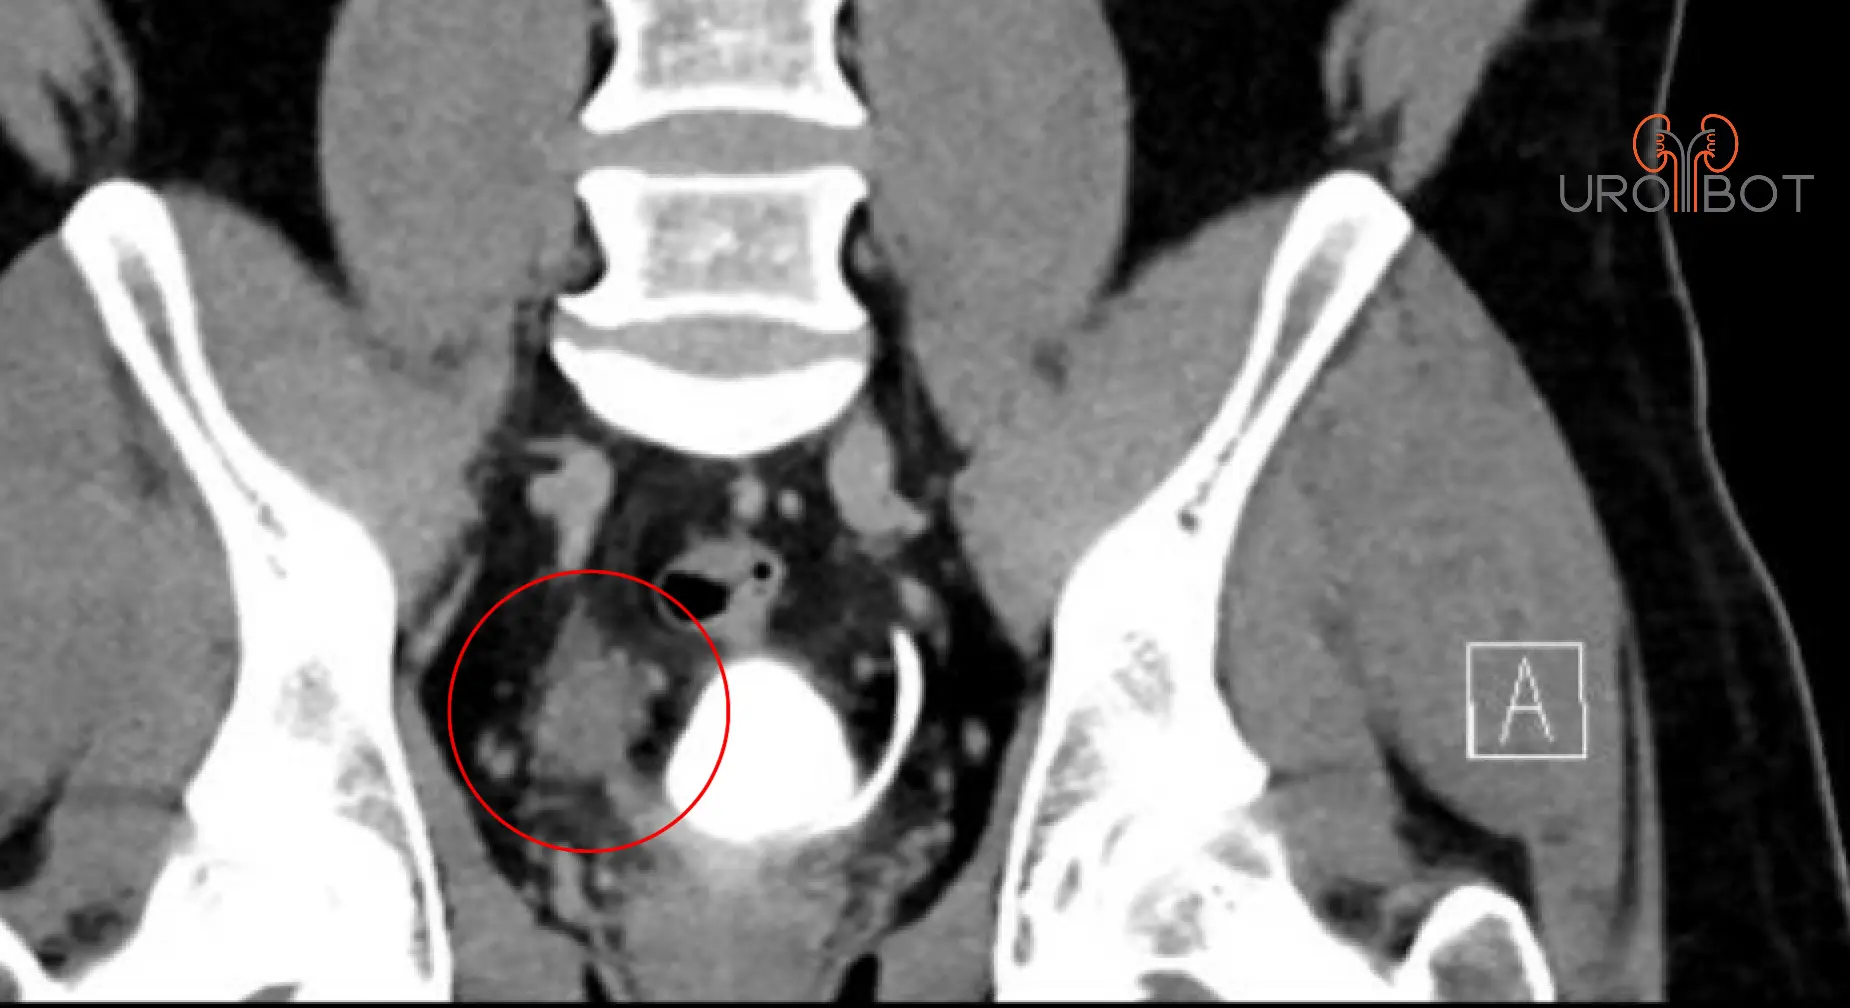

Harnleiterkarzinom

Bei einer Harnleiterteilresektion wird ein Teil des Harnleiters entfernt, weil er zum Beispiel durch einen Tumor befallen ist oder wegen einer Verengung nicht mehr durchgängig ist.

In Abhängigkeit der Lage im Harnleiter kann die Blase "verlängert" und hochgezogen werden oder der Harnleiter wird durch ein Stück Darm ersetzt.

Das nachfolgende Op-Video zeigt eine rechtsseitige distale Harnleiterteilresektion mit Harnleiterneueinpflanzung in der Psoas Hitch OP-Technik. Dazu wird die Harnblase auf der entsprechenden Seite nach seitlich nach oben gezogen und auf dem Musculus psoas befestigt, um die entfernte Harnleiterstrecke zu überbrücken.